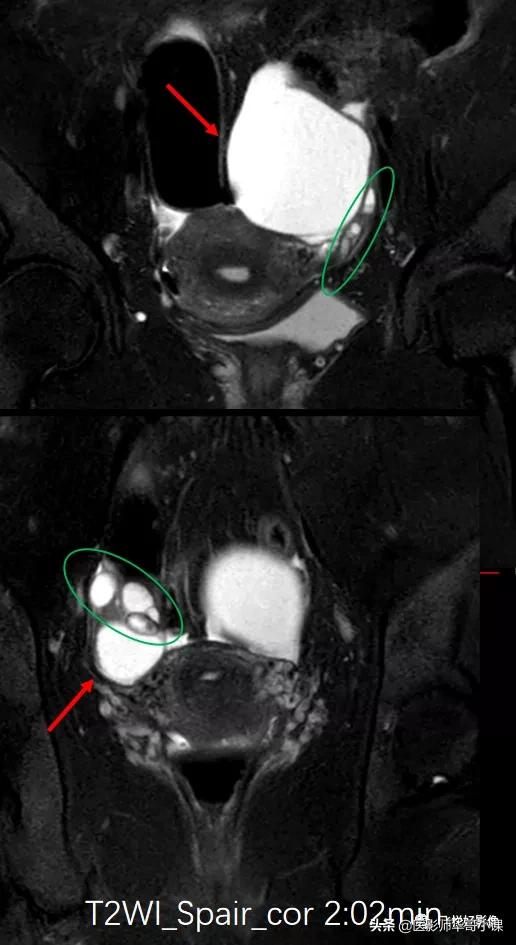

![[飞利浦磁共振技术]磁共振扫描下的“女性输卵管成像”,看视频吧](https://cdn.mendezhlauren156.workers.dev/origin/pgc-image/be090e2ece324d17aba22fd170113823.jpg)

图2.T2WI_SPAIR_COR

T2W_SPAIR横断位及冠状位图像(图1&图2)可以看到,盆腔双侧附件区见两个类圆形占位性病变,T2WI压脂高信号,边界清晰,边缘光滑,其内信号均匀,未见明确实性信号,病变与卵巢关系密切。